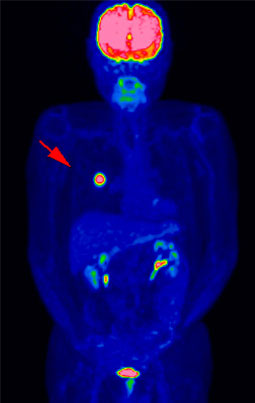

▲早期右乳癌